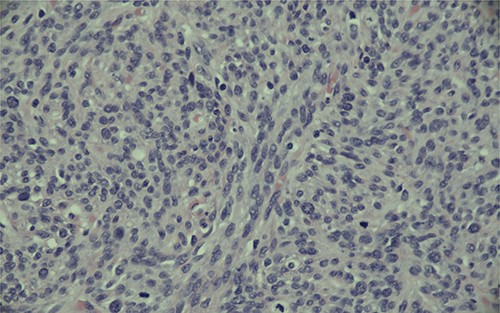

Magnification (40x) of histologic section of prostate, showing STUMP (upper left of image) and adjacent sarcoma (lower right of image).